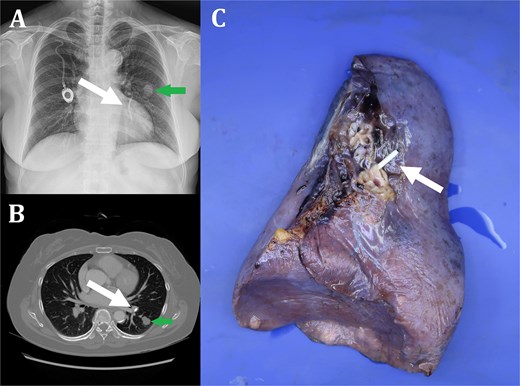

A 59-year-old female presented to our clinic for evaluation of left lung nodule. She underwent surgery for gastric cancer (Stage IIIA) and chemoport was inserted in the right subclavian vein for adjuvant chemotherapy 10 years ago. A chest computed tomography (CT) scan revealed a 1.8 × 1.5 × 1.5 cm lobulating mass with slightly irregular margins in the superior segment of left lower lobe (LLL) (Fig. 1A and B). A CT-guided percutaneous needle biopsy was performed and colloid adenocarcinoma was diagnosed. At the same time, fractured chemoport fragment, which was embedded in left superior segmental pulmonary artery, was also confirmed (Fig. 1A and B). Fortunately, the catheter fragment did not cause any symptoms such as dyspnea or arrhythmia. An F-18-fluoro-positron emission tomography (FDG-PET) showed no evidence of lymph node involvement or distant metastasis. Surgical resection was planned and LLL resection with mediastinal lymph node dissection was performed through uniportal video assisted thoracic surgery. Histopathological findings were consistent with the diagnosis of colloid adenocarcinoma without visceral pleural invasion, lymphovascular invasion, or regional lymph node metastasis, T1bN0M0 (Fig. 2). The chemoport fragment was also removed clearly (Fig. 1C). After lobectomy was completed, the port chamber with proximal catheter segment was removed. The patient had an uneventful postoperative course and was discharged on postoperative Day 5. He has been free of recurrence for 1-year follow-up.

Fractured chemoport fragment embedded in left superior segmental pulmonary artery (white arrow) (A: Chest X-ray, B: Chest CT, C: Specimen of left lower lobe). Colloid adenocarcinoma in superior segment of left lower lobe (green arrow) (A: Chest X-ray, B: Chest CT).